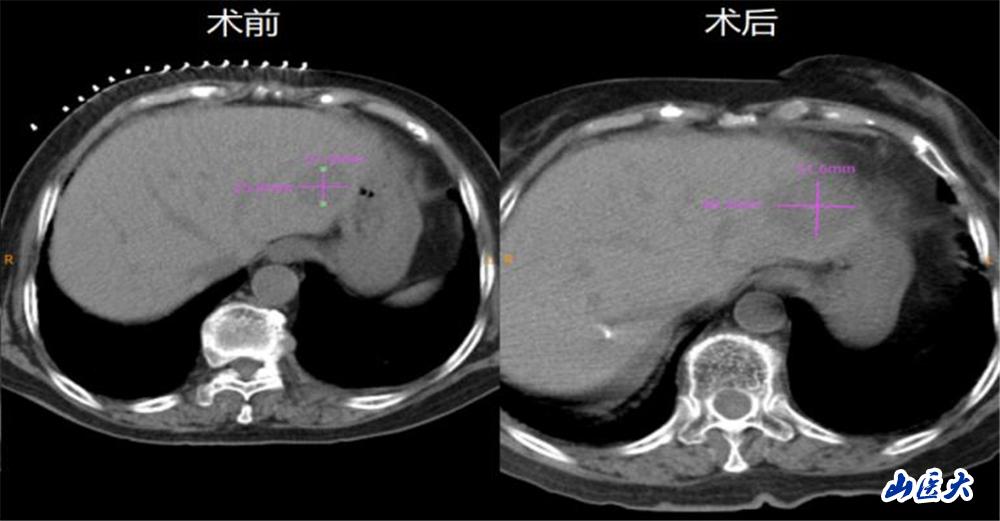

在介入手術室魏臻護士長帶領的護理團隊配合下,腫瘤科微創治療團隊成功為該患者進行了CT引導下經皮肝S2段轉移瘤微波消融治療。對比術前術后CT,消融范圍明確,且超出原并發灶邊緣5mm以上,達到了完全消融的效果。